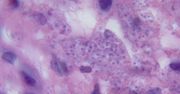

Leishmania – co to jest, objawy, leczenie